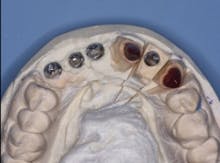

FIG. 4 — Custom cast abutments showing compensation for difficult angulation of implant placement.

FIG. 5 — Incisal view showing proper angulation of abutments.

Fig. 4 shows the parallelism of the three custom cast metal abutments on the patient’s maxillary right anterior area. These three abutments will be splinted together with a three-unit prosthesis. The prosthesis will be cemented with provisional cement (Premier Implant Cement). The cement will be placed only on the most apical third of each abutment when they are cemented to allow subsequent removal of the prosthesis in the event of loose screws or other challenges. Designing abutments to allow space for an optimum esthetic result demands communication between the dentist and lab technician. Fig. 5 demonstrates the homogeneous potential thickness of the subsequent restorations to be placed.